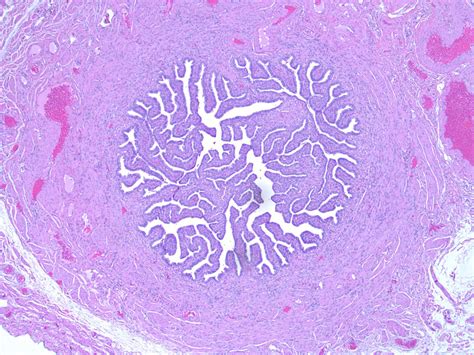

The Fallopian tube uterine tube structures are approximately 10 to 12 centimeters in length and are located on either side of the uterus. They are not merely simple pipes; they are complex organs divided into four distinct anatomical regions, each with specific functions designed to facilitate fertilization.

• Infundibulum: The funnel-shaped distal end near the ovary, featuring finger-like projections called fimbriae that "catch" the egg upon ovulation.

• Ampulla: The widest and longest section of the tube. This is where fertilization typically occurs when sperm meets the ovum.

• Isthmus: A narrow, thick-walled portion that connects the ampulla to the uterine cavity.

• Uterine part (Intramural): The segment that passes through the wall of the uterus to open into the uterine cavity.